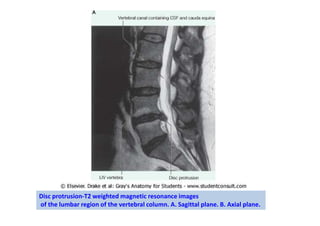

Disc protrusion-T2 weighted magnetic resonance images

of the lumbar region of the vertebral column. A. Sagittal plane. B. Axial plane.